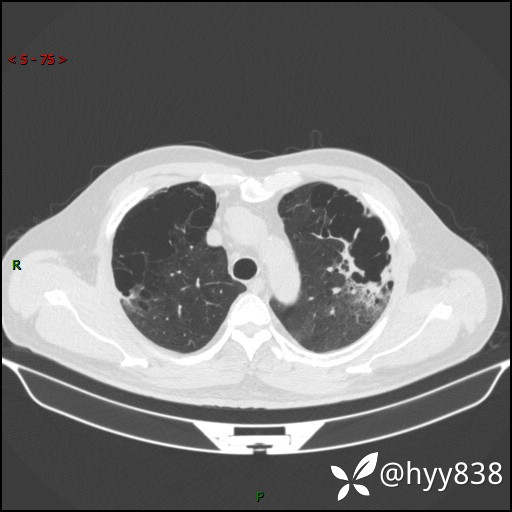

一周后胸部CT